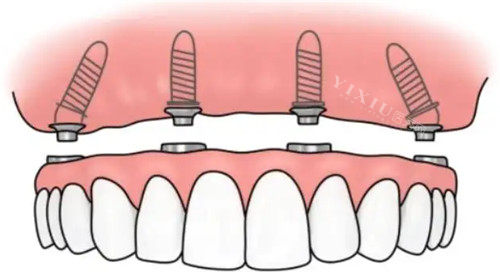

半口种植牙(6颗植体基础套餐):25000元起

半口种植牙(8颗植体中端套餐):40000元起

全口种植牙(12颗植体基础套餐):45000元起

全口种植牙(16颗植体高端套餐):90000元起